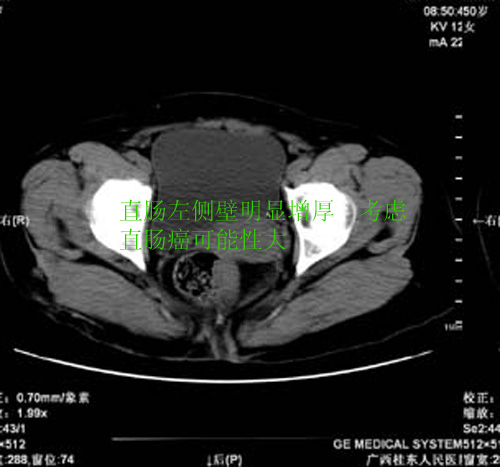

患者,女 50岁.会阴部坠胀感一月余,有痔疮病史,近期有便血;患者今年5月分结肠镜检查未见异常(由于患者不愿意ct增强扫描)没做增强,现准备手术,请各位老师会诊.

直肠壁明显增厚,呈块状表现,肠腔狭窄闭塞,考虑ca

直肠壁增厚明显,周围脂肪间隙模糊,见有小淋巴结显示,前方与阴道后壁分解不清。考虑直肠癌可能性大

不做强化,但平扫保留灌肠一定要做好。现在看直肠壁增厚明显,周围脂肪间隙模糊,前方与阴道后壁分界不清。考虑直肠癌可能性大

直肠左侧壁明显增厚,考虑直肠癌可能性大.